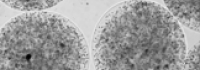

Purtroppo l’attuale terapia farmacologica per l'Huntington non consente ancora di rallentare il decorso della malattia. Nello studio sperimentale appena pubblicato sono state sfruttate le proprietà immunomodulatorie, antiinfiammatorie e trofiche di una particolare cellula del testicolo del maiale, la cellula di Sèrtoli, che normalmente svolge, nella sua sede fisiologica, funzioni nutritizie e protettive sulla spermatogenesi. Cellule di Sertoli ottenute da un allevamento di suini tenuti in condizioni di assoluta assenza di agenti infettivi sono state immobilizzate all’interno di microscopiche capsule di alginato di sodio già approvato per uso umano. Le cellule microincapsulate sono state quindi iniettate nel cavo peritoneale (addome) di topi affetti da Malattia di Huntington.

“Le microcapsule contenenti cellule di Sertoli – dichiarano i ricercatori - agiscono come una microfabbrica biologica che dalla cavità peritoneale rilascia fattori i quali, per via sistemica, possono raggiungere le parti malate, senza la necessità di iniezioni locali nel Sistema Nervoso e senza richiedere immunosoppressione farmacologica. Due grandi vantaggi che rendono il protocollo terapeutico particolarmente promettente.”

Nella foto: le microcapsule contenenti le cellule di Sertoli utilizzate nel presente studio. Le microscopiche capsule hanno dimensioni di circa 0,5 mm di diametro.